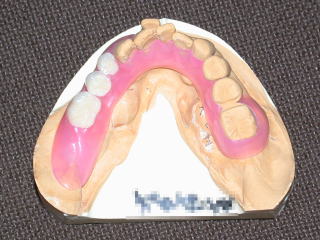

平成28年11月15日 下顎のみクラスプレスデンチャー装着しました。

今回は下顎隆起(外骨症)が大きく、のみピタッとしないので、下顎のみクラスプレスデンチャー作成、装着です。